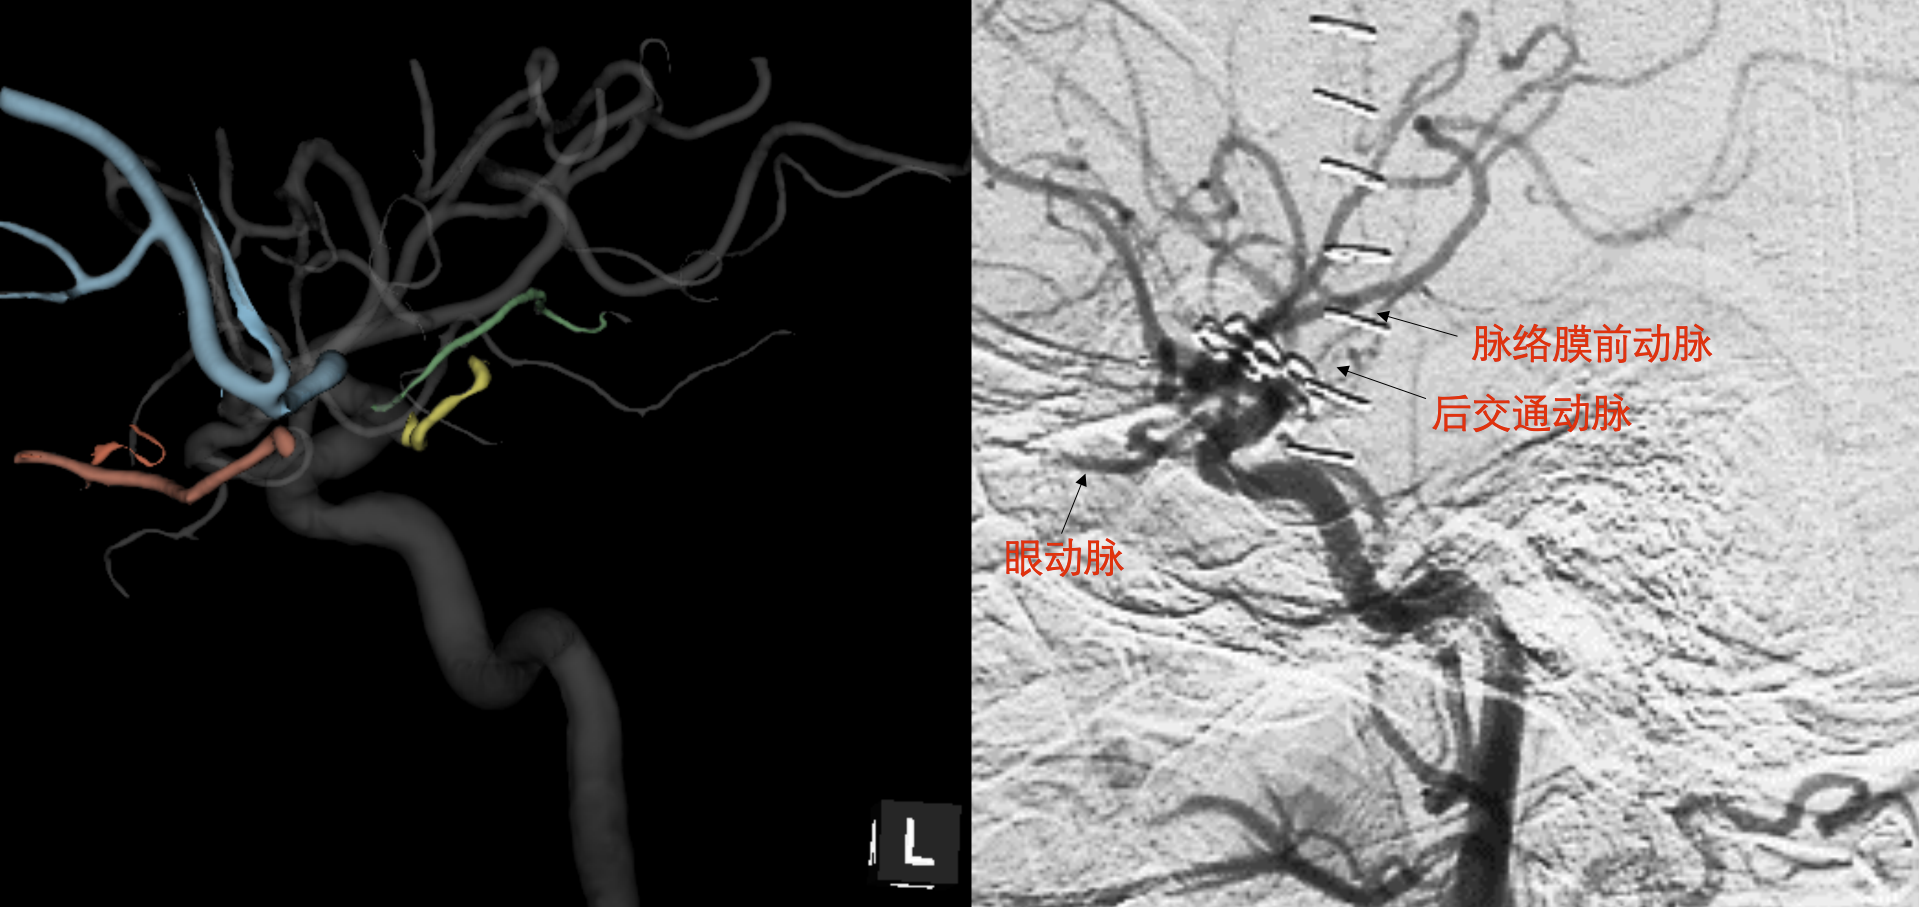

79b9182e2265605102fa72b2aac1e347.png

前后位(AP)三维影像和DSA对比,在有三维影像参考的提前下,DSA平片能很快判断出脉络前、后交通等显影不佳的细小动脉

67cc0e5a5d731917a13959b3b31e9167.png

侧位(LR)DSA平片上由于血管重叠,很难判断大脑中和大脑前的分支血管,但有利于观察前后走行的动脉,如:眼动脉,后交通动脉、脉络膜动脉等